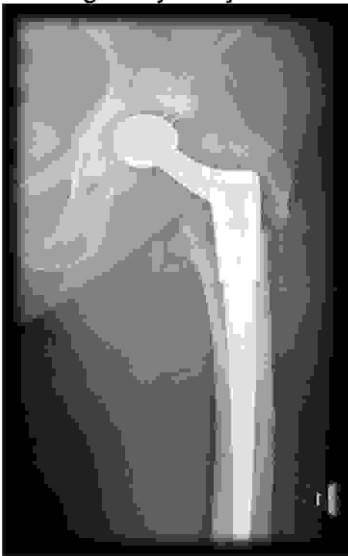

Przedstawiony poniżej radiogram obrazuje złamanie okołoprotezowe. Według klasyfikacji Vancouver jest to typ złamania: